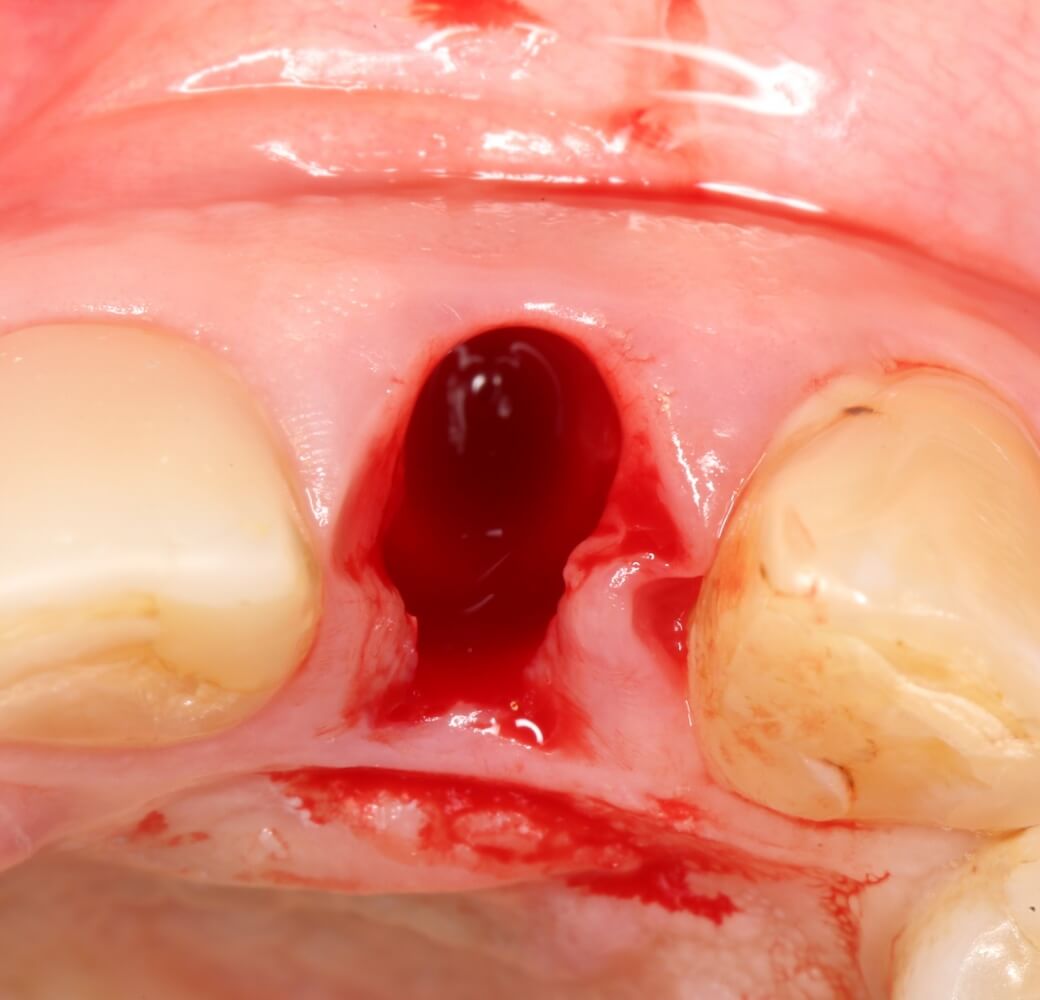

Разумеется, мы можем на неё влиять. Так, немедленная имплантация и превентивная аугментация лунки уменьшают степень атрофии, хотя и не предотвращают ее полностью:

В целом, заметна статистическая разница между спонтанным (обычным) заживлением лунки и заживлением после превентивной аугментации. Это исследование провели в Цюрихском Университете (prof. D. Thoma et al):